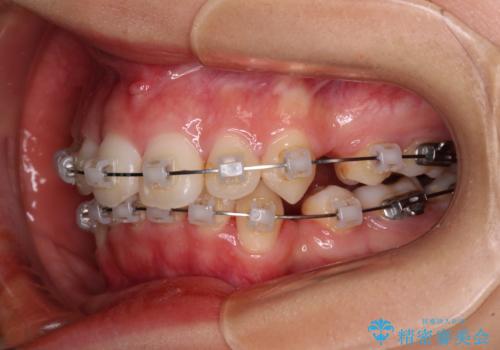

補助装置を用いて奥歯の咬み合わせを改善しながら歯列を後方に移動させ、上下左右第一小臼歯を4本抜歯することで八重歯や口元の突出感を改善することとしました。

奥歯の咬み合わせの不正が顕著であったため、表側のワイヤー装置を選択して矯正治療を行うこととしました。